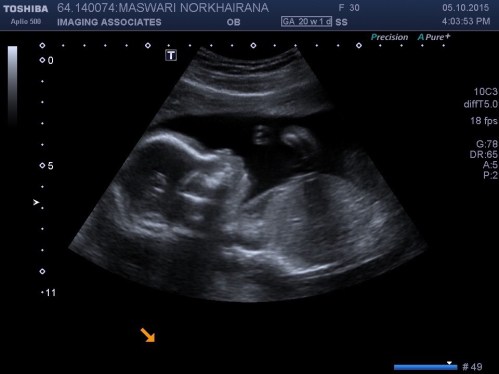

Oh wells, on a brighter note i am on to my 27th week! Super exciting and at the same time nerve wrecking! The photo below was taken last week! Mummy will try her hardest to provide the best for you baby! Can’t wait to have you in my arms 😘